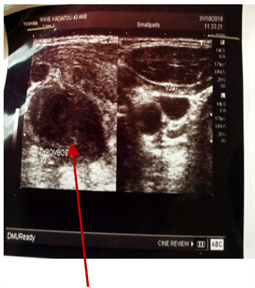

This patient was a 40-year-old housewife with dysphonia, physical asthenia, palpitations, fever and cervical tumefaction (Figure 1) that had been going on for 2 months. As an antecedent ischemic stroke without cardiovascular risk factor. Heart sounds were regular at 110 bpm, blood pressure = 120/80 mmhg, to the lungs there are sibilant rattles. Elsewhere, there is a painful left lateral cervical tumefaction febrile to the touch. Temperature = 38˚C. The rest of the exam is peculiar. Electrocardiogram showed sinus tachycardia. Ultrasonography of the neck resulted in a normal ultrasonic appearance of the thyroid glands, total thrombosis of the right jugular vein associated with ipsilateral lymphadenopathy (Figure 2). Venous doppler echo of the neck concluded with thrombosis of the acute right jugular vein. Cardiac Echodoppler was normal. The biology revealed

Figure 2. Ultrasound of the neck showing a normal ultrasonic appearance of the thyroid glands, total thrombosis of the right jugular vein associated with ipsilateral lymphadenopathy.